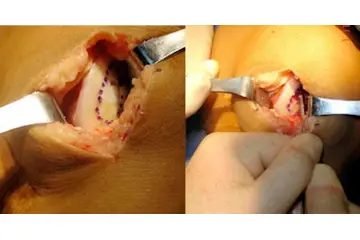

Diz Kıkırdak Hasarının Tanısı Diz kıkırdak hasarının tanısı, genellikle bir ortopedi uzmanı tarafından konulur. Tanı sürecinde şu yöntemler kullanılabilir:

Diz Kıkırdak Hasarının Tedavi Yöntemleri Diz kıkırdak hasarının tedavisi, hasarın ciddiyetine ve bireyin genel sağlık durumuna bağlı olarak değişir. Tedavi yöntemleri arasında şunlar bulunmaktadır: